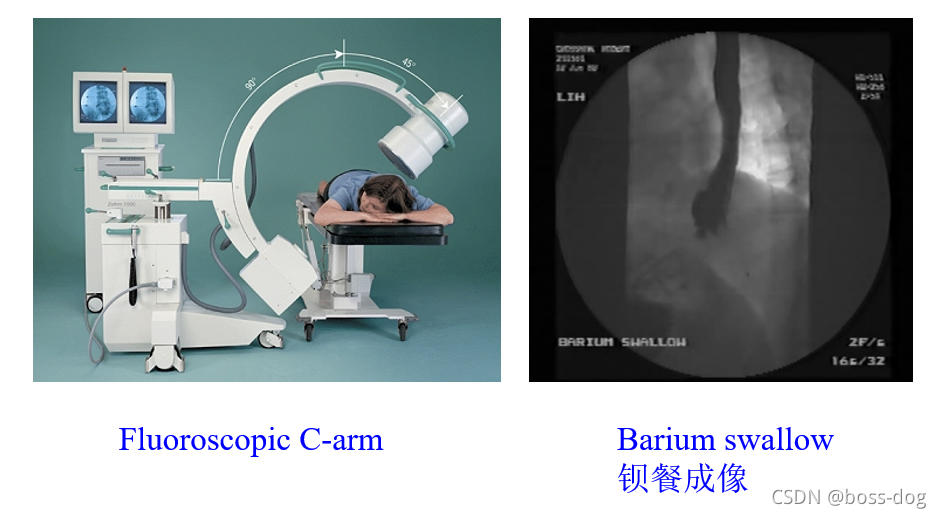

Fluoroscopy—Real time radiography(荧光成像——实时的X光成像)

上图通过打钡对比剂。